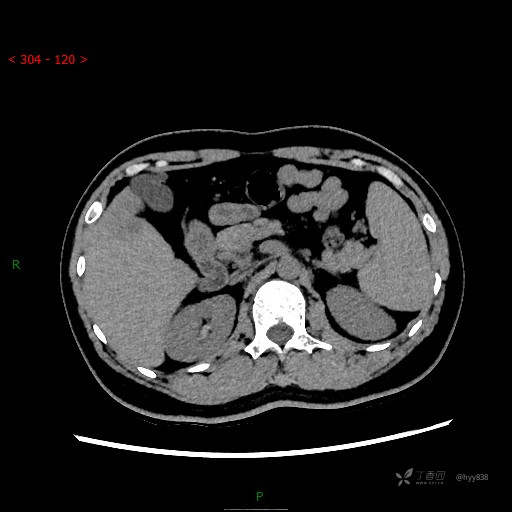

门脉期